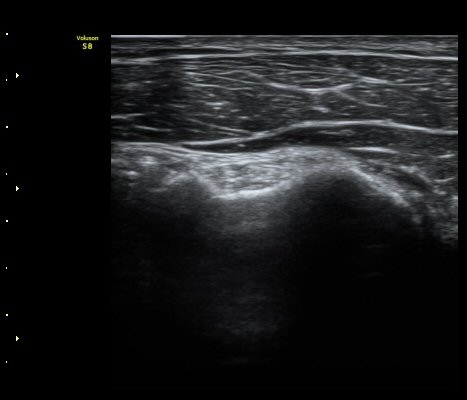

¿À±¸µ¹±â Ⱦ´Ü¸é°Ë»ç»ó ¿Áµ¹±â ¾Æ·¡, ³»Ãø, °ß°©ÇÏ±Ù°Ç Ç¥Ãþ¿¡¼­ ¼ö¾×Àú·ù°¡ °üÂûµÈ´Ù

(±×¸² 3, 4).